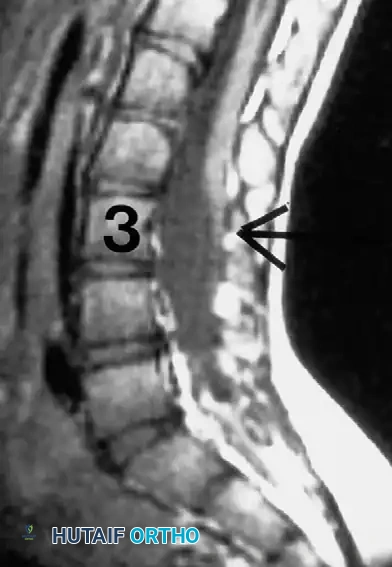

In patients with progressive paralytic scoliosis, the surgeon must maintain a high index of suspicion for intraspinal anomalies. Hydromyelia, a malfunctioning ventricular shunt, syringomyelia, or compression from an Arnold-Chiari syndrome can rapidly accelerate curve progression.

Lubicky astutely noted that almost all patients with myelomeningocele exhibit radiographic evidence of spinal cord tethering at the site of the primary sac closure.

SURGICAL WARNING: The mere presence of radiographic tethering on MRI does not automatically imply pathological traction on the cord. The surgeon must look for corroborating clinical signs of tethering, which include: new-onset back pain, increased lower extremity spasticity, rapid changes in muscle strength, deteriorating gait, acute changes in bowel/bladder function, or the sudden appearance of foot deformities (e.g., cavovarus).

* Advanced Imaging: MRI is mandatory to evaluate for hydromyelia, tethered cord, diastematomyelia, and Arnold-Chiari malformations. Intravenous pyelography or renal ultrasound should be updated per urological recommendations to map ureteral anatomy prior to anterior spinal approaches.